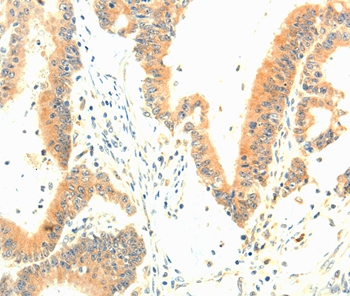

Immunohistochemical analysis of paraffin-embedded Human colon cancer tissue using #35974 at dilution 1/30.

Immunohistochemistry: 1:25-1:100